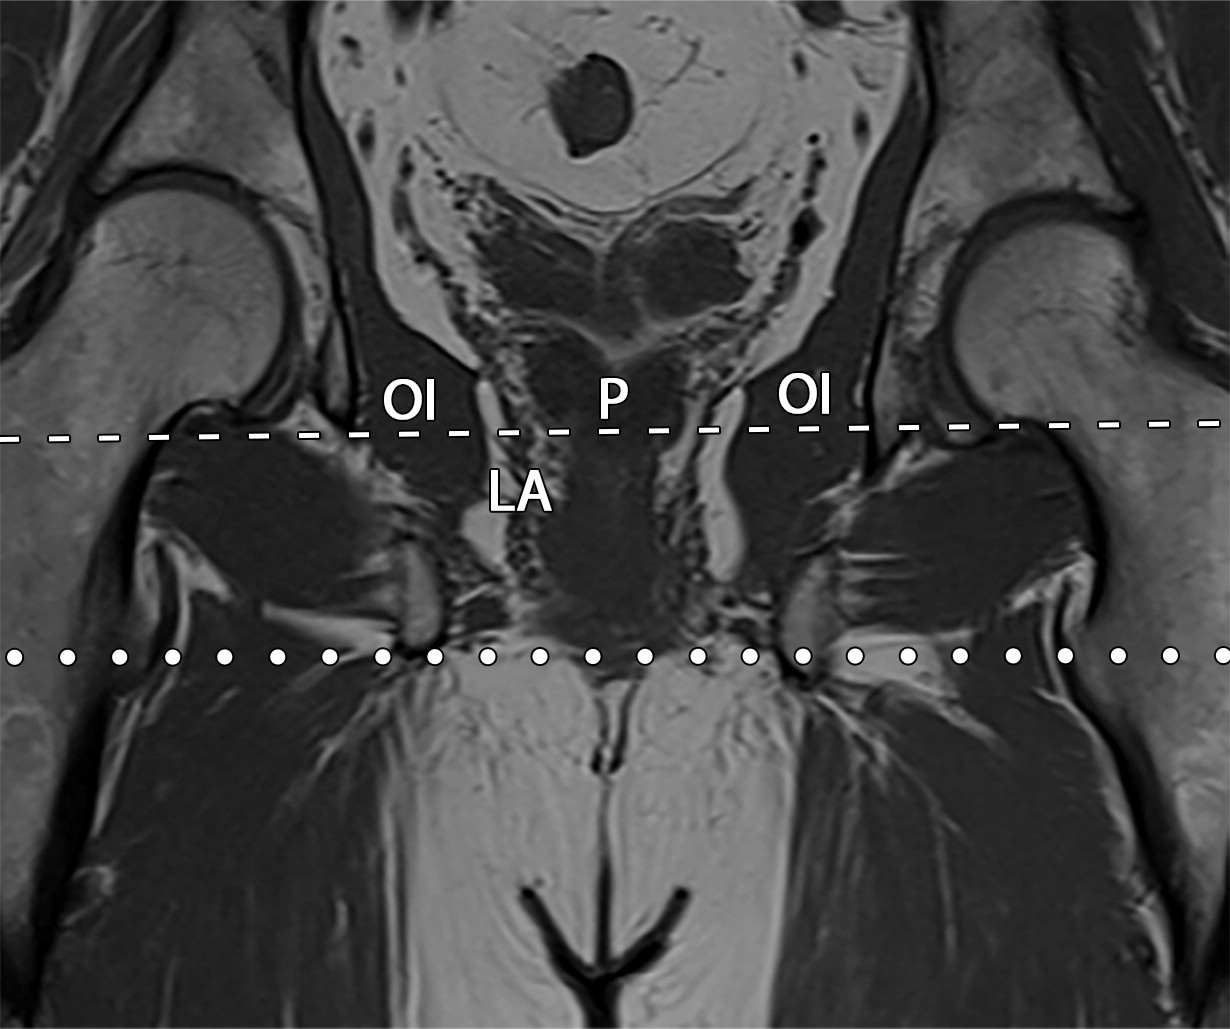

50岁以上男性骨盆和盆底的MRI解剖。

提肛肌(LA),由耻骨直肠肌(PR)、耻骨尾骨肌(PC)和髂尾骨肌(IC)组成;尾骨肌(C),前列腺(P),闭孔内肌(OI),会阴浅横肌(STP),球海绵体肌 (B), 坐骨海绵体肌(ISC),肛门外括约肌(EAS),肛门内括约肌(IAS),直肠(R),尿道括约肌(SU),也称为尿道外括约肌(U),它包围着整个膜性尿道。6774449af17bb1b8df6e83ab4e9fa158.jpeg